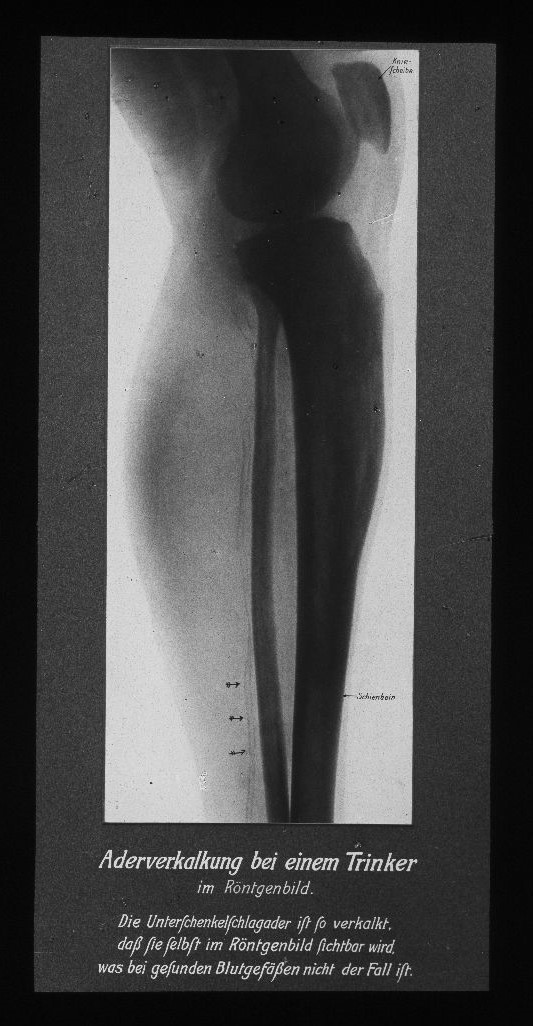

Von der Fettleber bis zur Schrumpfniere. Monokausale Zusammenhänge und Schuldzuweisung

„Der Alkohohol – Dein Feind!“ Auch der Diskurs über die körperliche Schädigung des Alkohols zielte in der sozialdemokratischen Antialkoholpolitik auf die Gesundheit des „Volkes“ ab. Die Bevölkerung sollte zur Abstinenz erzogen werden, Gesundheit war moralische Arbeit und Abweichung von der Moral hatte Krankheiten zur Folge. Der Terminus „Trinker“ war unscharf: Es erfolgte keine Unterscheidung zwischen Alkoholmissbrauch, Alkoholabhängigkeit und gelegentlichem Alkoholkonsum. Die abschreckenden Bilder degenerierter innerer Organe und Medizinalstatistiken waren ein Appell an die Moral.